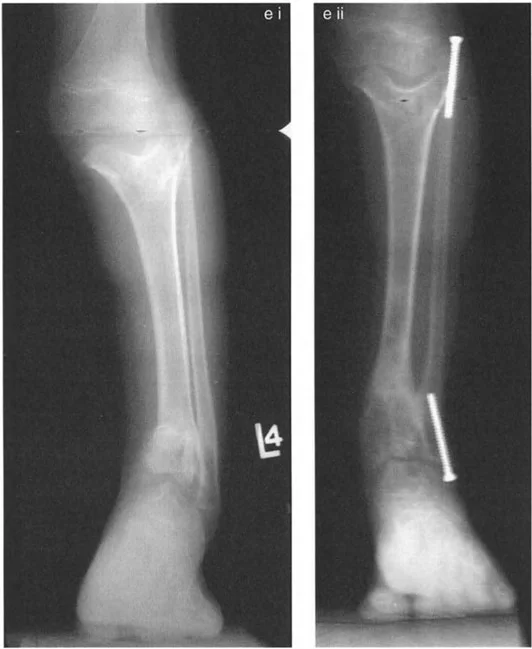

* الكسور غير الملتئمة أو الملتئمة بشكل خاطئ: إذا لم يتم علاج كسر في الجزء السفلي من قصبة الساق أو الكاحل بشكل صحيح، أو إذا حدث التئام للعظم في وضع غير طبيعي، فقد يؤدي ذلك إلى تشوه دائم. على سبيل المثال، كسر في الكاحل يلتئم مع تقوس (Varus) أو روحبة (Valgus) في قصبة الساق يمكن أن يغير ميكانيكا الكاحل بشكل جذري.

* إصابات صفيحة النمو (Physeal Injuries): لدى الأطفال والمراهقين، يمكن أن تؤدي الإصابات التي تلحق بصفيحة النمو (المنطقة المسؤولة عن نمو العظم) إلى توقف النمو في جزء من الصفيحة، مما يتسبب في نمو العظم بشكل غير متساوٍ وتشوه.

* الأشعة السينية الجانبية والامامية الخلفية للكاحل: تُظهر هذه الصور تفاصيل مفصل الكاحل نفسه، بما في ذلك زاوية القصبة الأمامية البعيدة (ADTA) وزاوية القصبة الوحشية البعيدة (LDTA)، وهي زوايا حاسمة لتحديد التشوه في المستويين الأمامي والسهمي.

جراحة قطع العظم فوق الكاحل (SMO) هي الإجراء الأكثر شيوعًا لتصحيح تشوهات قصبة الساق البعيدة. تتضمن هذه الجراحة قطعًا دقيقًا في عظم الساق (القصبة) فوق مفصل الكاحل مباشرة، ثم إعادة محاذاة العظم وتثبيته في الوضع الصحيح. هناك عدة أنواع من هذه الجراحة: